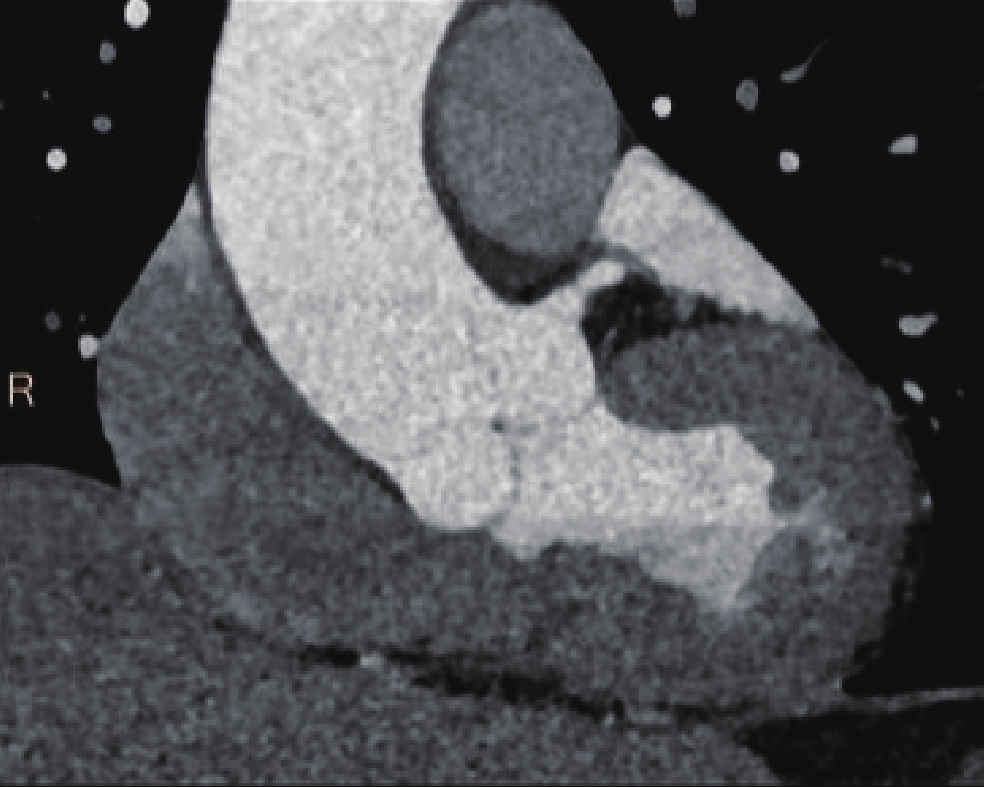

• 摘要: 目的:探讨不同扫描模式对胸主动脉CTA图像质量和辐射剂量的影响。方法:回顾性分析未应用心电门控技术的30例胸主动脉CTA(组1,对照组),使用回顾性心电门控的30例冠脉CTA重建舒张期(组2)和收缩期(组3)时相,30例应用宽曝光脉冲前瞻性心电门控技术(组4)共4组图像的质量和辐射剂量。分别记录、计算4组的图像质量客观指标CT值、噪声、CNR和辐射剂量指标CTDIvol。对图像质量进行四分法主观评价。对主客观指标分别统计分析。结果:客观指标CNR组1与组2、3、4均有差异,组2、3、4间均无差异;主观评分两两比较组2~4显著高于组1,组2~4间无差异。非门控组(组1)、回顾门控组(组2和组3)和前瞻门控组(组4)的CTDIvol分别为13.70(11.87,16.58)、12.62(10.03,15.01)、11.54(8.92,15.56),差异无统计学意义。结论:在胸主动脉CTA中推荐使用窄曝光脉冲的前瞻性心电门控收缩期或舒张期扫描,可显著提高胸主动脉心脏段图像质量并降低辐射剂量。

Abstract: Objective: This study aimed to compare the effects of different scanning modes on image quality and radiation dose in thoracic aortic computed tomography angiography (CTA). Methods: The image quality and radiation dose of 30 cases of thoracic aortic CTA (Group 1, control group), 30 cases of retrospective CTA diastolic phase (Group 2) and systolic phase (Group 3), and 30 cases of wide-exposure pulse prospective electrocardiogram (ECG) (Group 4) were retrospectively analyzed. The CT value, noise, contrast-to-noise ratio (CNR), signal-to-noise ratio (SNR), and radiation dose (volume CT dose index CTDIvol) were recorded and measured. The image quality was evaluated subjectively using the four points method. The subjective and objective indicators were analyzed statistically. Results: No differences were observed in the objective indexes of noise, CNR and SNR among the groups. The subjective score of pairwise comparison of Groups 2~4 was significantly higher than that of Group 1, and no difference was observed among Groups 2~4. The CTDIvol values of the non-gated group (Group 1), retrospective gated groups (Groups 2 and 3), and prospective gated group (Group 4) were 13.70 (11.87,16.58), 12.62 (10.03,15.01), and 11.54 (8.92,15.56), respectively, without a statistically significant difference.